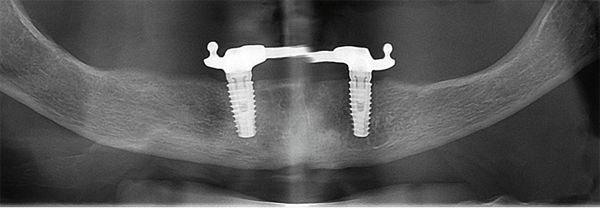

A perda óssea, denominada saucerização, é um processo que ocorre em implantes osseointegrados, principalmente os de plataforma hexagonal externa e que não dependem necessariamente da condição geral do paciente. Perdas ósseas mínimas (entre 1 mm e 2 mm) são consideradas relativamente normais em implantes de plataforma hexagonal externa. Contudo, estudos realizados através de avaliações radiográficas constataram que o emprego da plataforma switching mantém os níveis da crista óssea estáveis com uma perda de osso mínima nesta área do hexágono2.

Muitos autores consideram os implantes conhecidos como Cone Morse como sendo implantes de plataforma switching, pois o verdadeiro conceito Cone Morse, descrito na Engenharia, é muito difícil de ser obtido na Implantodontia. Na verdade, os implantes Cone Morse também procuram aumentar a área de transição entre o implante e o pilar através de uma diminuição da largura dos componentes protéticos. As vantagens são exatamente as mesmas: proporcionar uma melhor área para a acomodação dos componentes do espaço biológico e evitar perdas ósseas precoces. As Figuras 1 a 4 ilustram o conceito de plataforma switching.